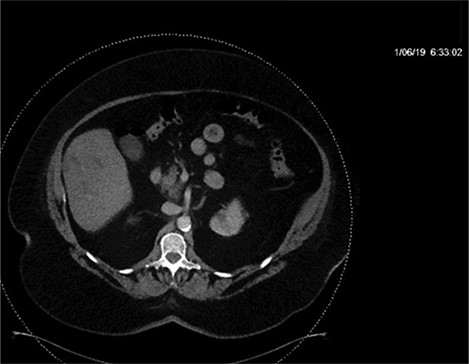

CT of the abdomen and pelvis with IV contrast was performed within 2 h of presentation. The scan showed “indeterminate, scattered ill-defined hypo-enhancing lesions in the liver with no acute etiology identified to explain the patient’s abdominal pain” (Figs 1, 3, 5). The remainder of the CT was unremarkable. Ultrasound (US) of the abdomen was negative. Because the CT and US did not identify an etiology for the patient’s abdominal pain, the working diagnosis at that time was an intestinal obstructive process.

CT with IV contrast taken at 0633 which shows ill defined, hypo-enhanced lesions of the liver.